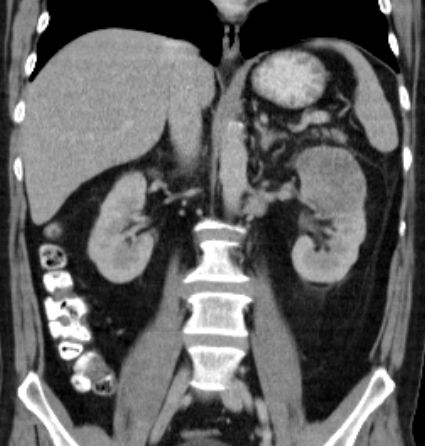

| Nierenzell-Karzinom C64 | Im CT nach Kontrastmittelgabe ein

Nierenzellkarzinom links erkennbar.![]() | ||